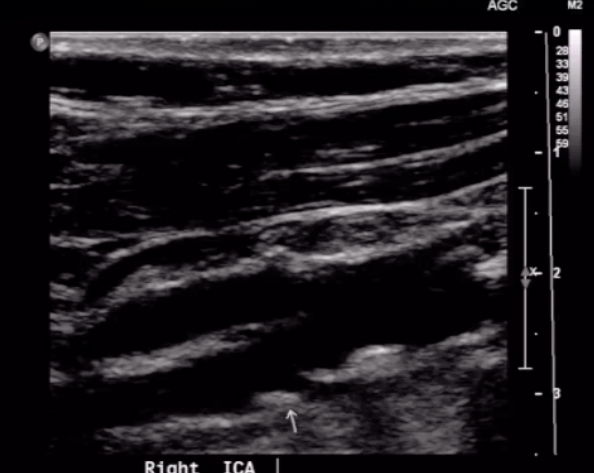

Carotid DUS imaging shown below. Diagnosis?

near-total ICA occlusion

note significant ICA plaque with low velocities distal to lesion (“falling off spencer-reid curve”)